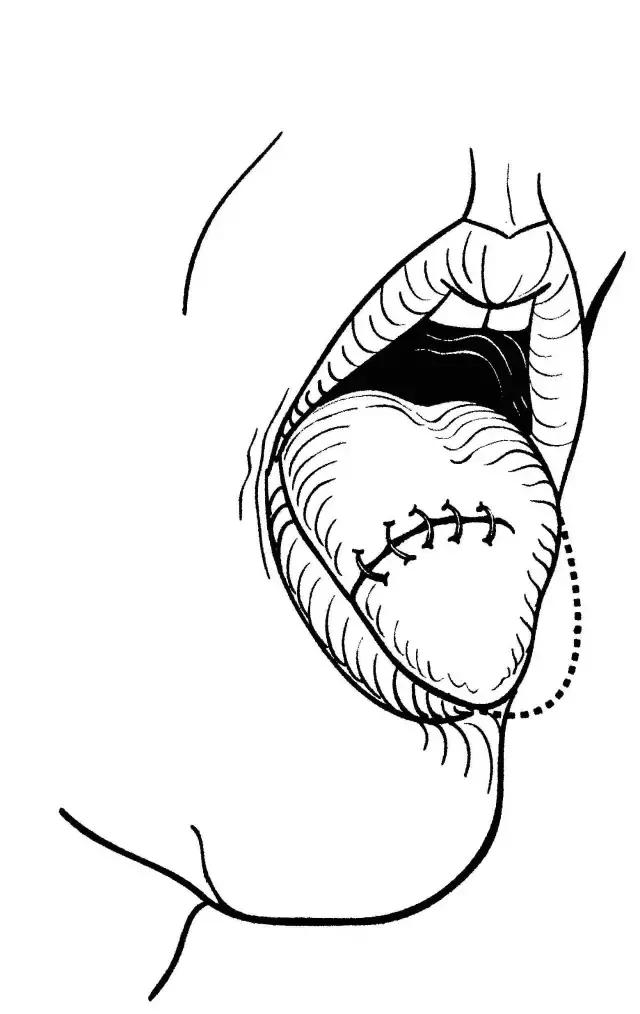

舌癌的经口楔形切除术